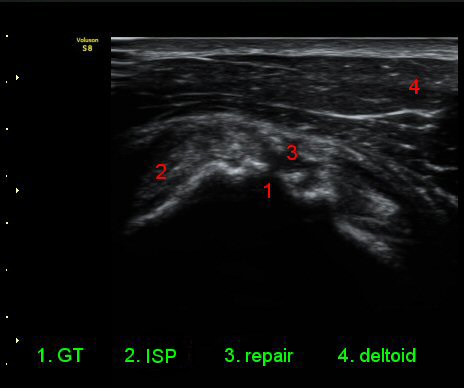

¾î±ú¸¦ ³»Àü, ³»È¸Àü, ½ÅÀüÇÏ¿© ±Ø»ó°Ç°Ë»ç¿¡¼­ ±Ø»ó°Ç ÆÄ¿­ ÈÄ ¼ö¼úÇÑ ¼Ò°ß, ±Ø»ó°ÇÀÇ

Àú¿¡ÄÚ ºÎÁ¾°ú ºÎºÐÀû ÆÄ¿­, °í¿¡ÄÚ ºÀÇÕ»ç, ´ë°áÀýÀÇ ºÒ±ÔÄ¢º¯È­,À» º¸¿©ÁØ´Ù(»çÁø 6, 7, 8, 9)